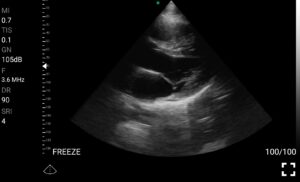

• Καρδιολογική Απεικόνιση για Κλινική Αξιολόγηση

• Εκτίμηση κλάσματος εξώθησης (EF): Προσέγγιση της συστολικής λειτουργίας της αριστερής κοιλίας.

• Διάγνωση περικαρδιακής συλλογής: Εκτίμηση πιθανής καρδιακής επιπωματισμού.

Παραδείγματα

Ολες οι παραπάνω απεικονιστικές εξετάσεις έχουν ληφθεί από φορητή συσκευή όπως: Apple Iphone, Tablet, Samsung Mobile Phones και διάφορες άλλες φορητές συσκευές.